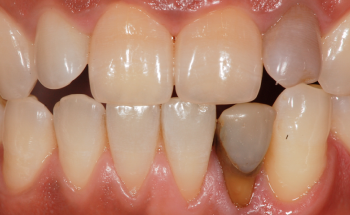

앞니 신경치료 후 치아미백, 크라운까지

신경치료 후 크라운 안하면 안되는 이유

앞니가 부러졌다면